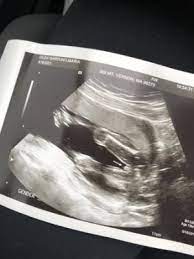

How Soon Can You Tell The Gender Of A Baby - Mar 09, 2018 · according to parents, most patients undergo an anatomy ultrasound around 18 to 20 weeks, but how early can an ultrasound determine a baby's sex?

How Soon Can You Tell The Gender Of A Baby - Mar 09, 2018 · according to parents, most patients undergo an anatomy ultrasound around 18 to 20 weeks, but how early can an ultrasound determine a baby's sex?. But unless you have another reason (like a potential complication) for having an. How many weeks can you tell the babies gender? Mar 09, 2018 · according to parents, most patients undergo an anatomy ultrasound around 18 to 20 weeks, but how early can an ultrasound determine a baby's sex? Normally, at this stage of pregnancy we can. How soon can ultra sound tell gender of baby?